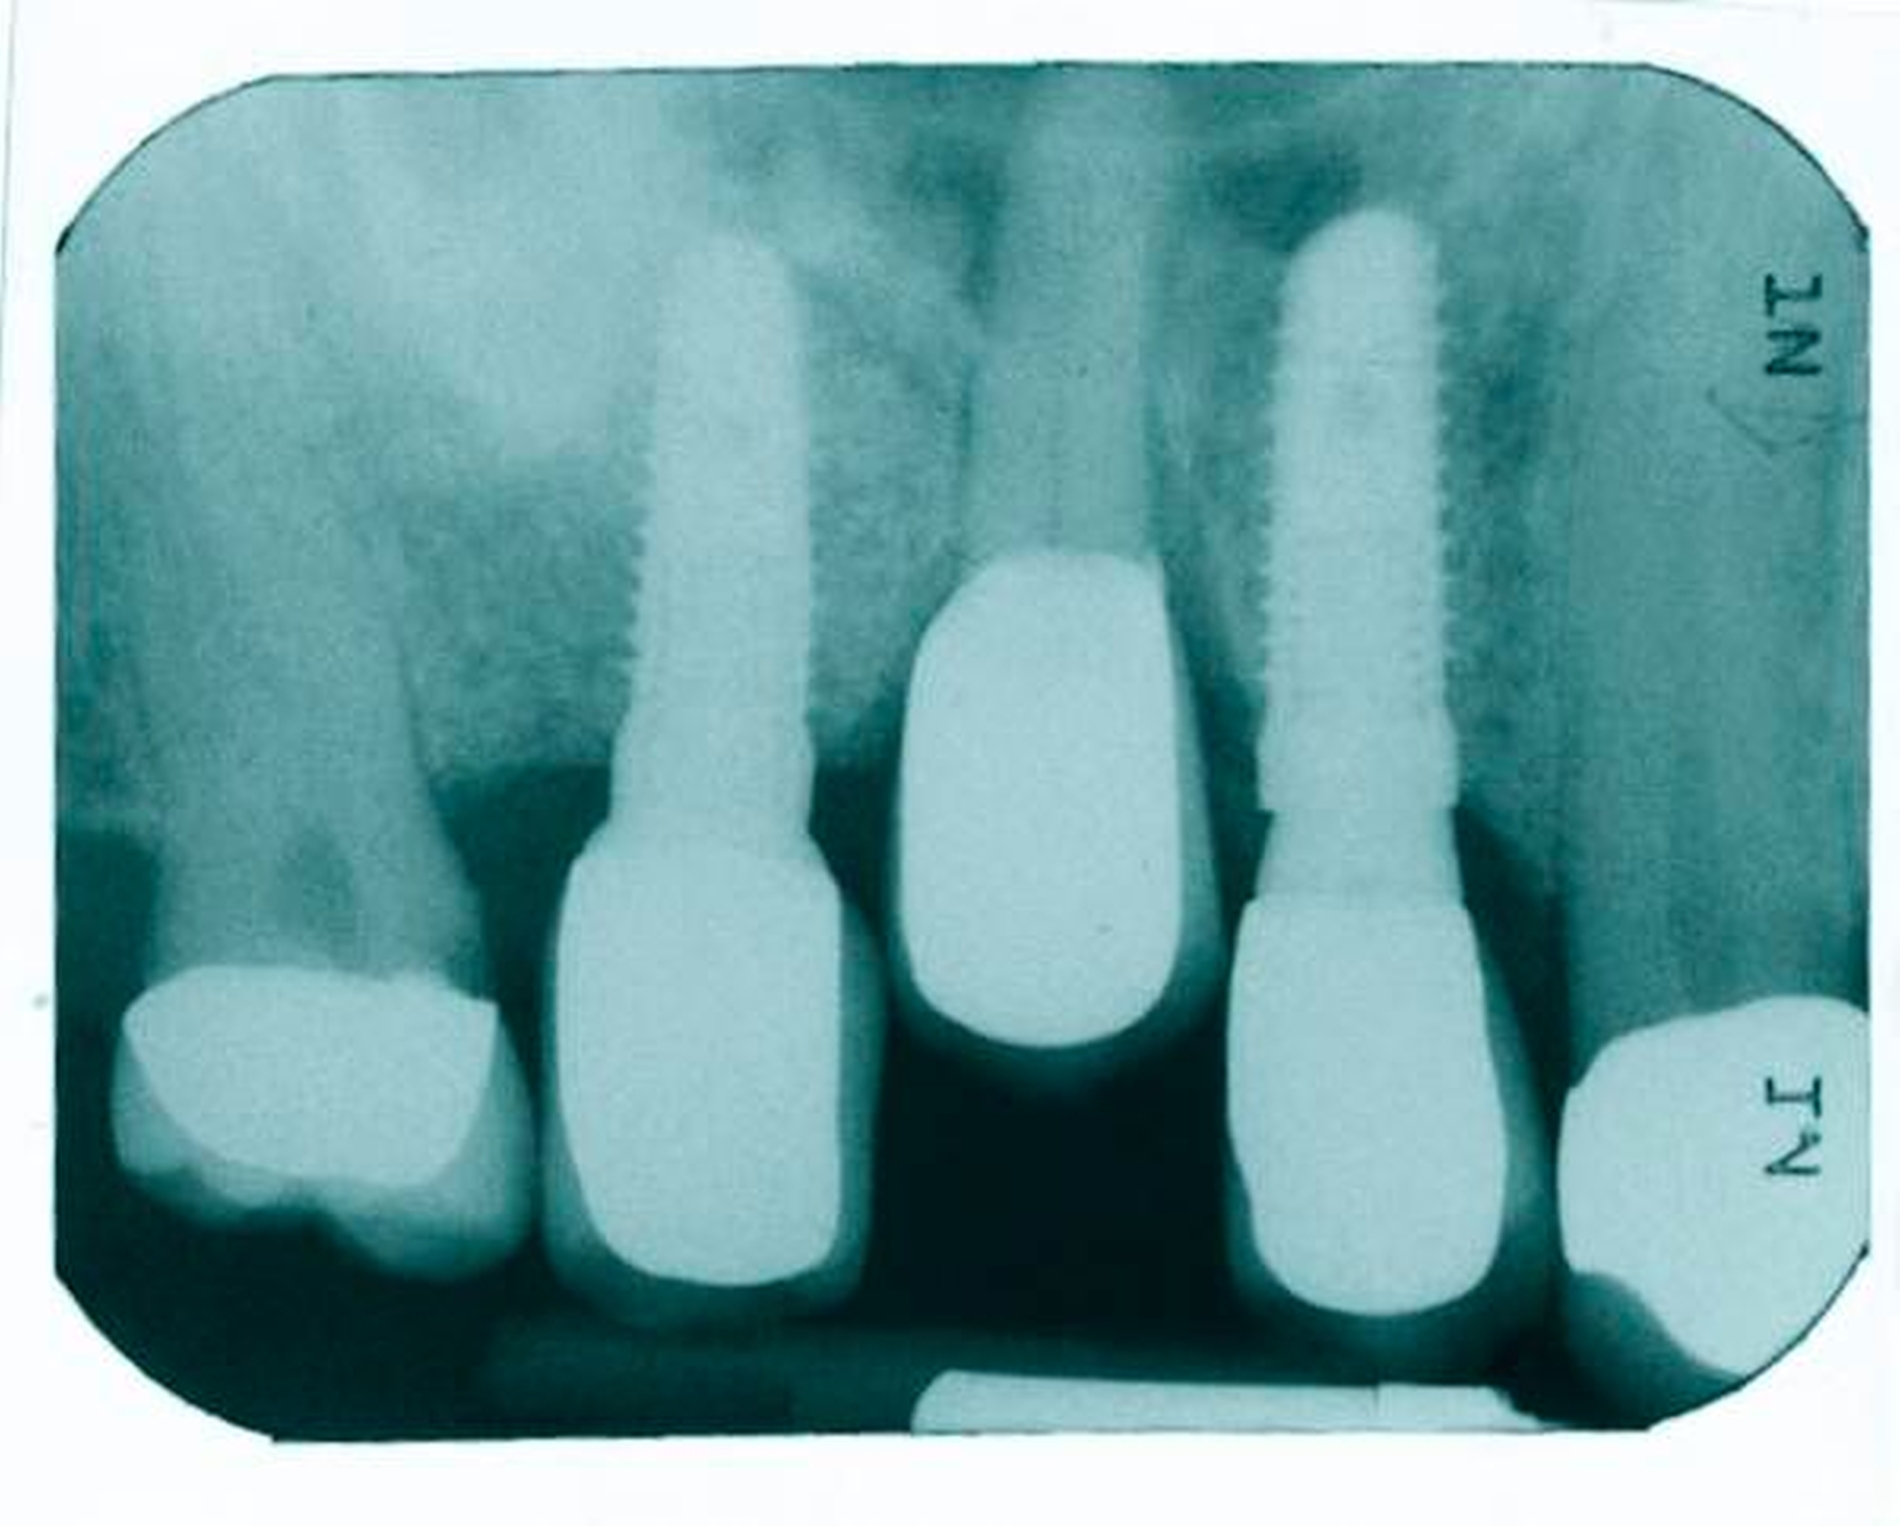

Die zweite Patientin, 75 Jahre alt, zeigte eine medikamentös eingestellte arterielle Hypertonie in der allgemeinen Anamnese. Sie hatte 2011 beidseits eine externe Sinusbodenelevation erhalten. Auch hier wurden Knochenersatzmaterial und autologer Knochen verwendet. Im Jahr 2012 folgte die Implantation von Titanimplantaten Regio 17, 14, 13, 23, 25, 27 für eine festsitzende Oberkieferversorgung.

Eine röntgenologische Routineuntersuchung ihres Zahnarztes ergab im April 2017 die vollständige Luxation des Implantats 17 in die Kieferhöhle direkt aus der prothetischen Versorgung heraus (Abbildung 3). Die Patientin hatte ebenfalls keine klinischen Beschwerden.